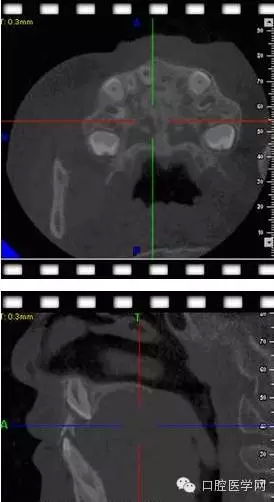

俺一般不喜歡浪費(fèi)國家資源,能拍小牙片的堅(jiān)決不拍CBCT.這個(gè)病例還真不敢輕易下刀。兩顆埋伏一二擠在一起,位置較深。讓步了,拍CT吧。

CBCT后影像

我們能夠更好的了解牙齒的立體空間結(jié)構(gòu).好東西哈,清晰。